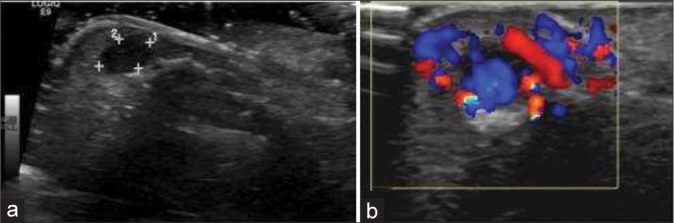

Soft tissue tumors involving the hand are common and most often benign. It is important to know the spectrum of soft tissue tumors of the hand and understand the typical as well as atypical imaging features are seen on different imaging modalities. The imaging features are largely determined by the tumor histopathology; thus, the basic idea about the tumor histopathology will always be useful. This article intends to focus on a comprehensive approach including demographics, clinical presentation, and imaging findings required to diagnose the tumor definitely or narrow the differentials. This article discusses common soft tissue tumor mimics of the hand as well, however, excludes the bone tumors for the sake of brevity.